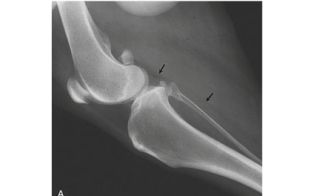

This video is part of a series of instructional videos designed to help new and experienced laser users effectively deliver laser therapy to specific joints. This video looks at that most challenging of joints, the stifle.

Dr. Ron Riegel, co-editor of Laser Therapy in Veterinary Medicine: Photobiomodulation demonstrates the techniques you need to maximize clinical benefit.